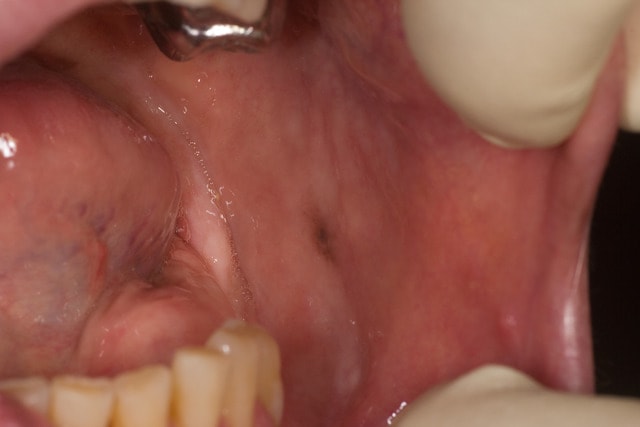

Juste pour information quelques photos de la maladie de Laugier . C'est relativement rare et aucun traitement n'est a faire hormis une surveillance .

C'est des taches mélaniques d'apparition aléatoire et qui restent en place.

Aucune evolution , connaitre ca c'est juste pour faire le DD avec des melanomes.

Concernant le qualificatif de "maladie" c'est vrai que comme c'est reelement benin certain l'appelle hyperpigmentation idiopathique et non pas maladie...